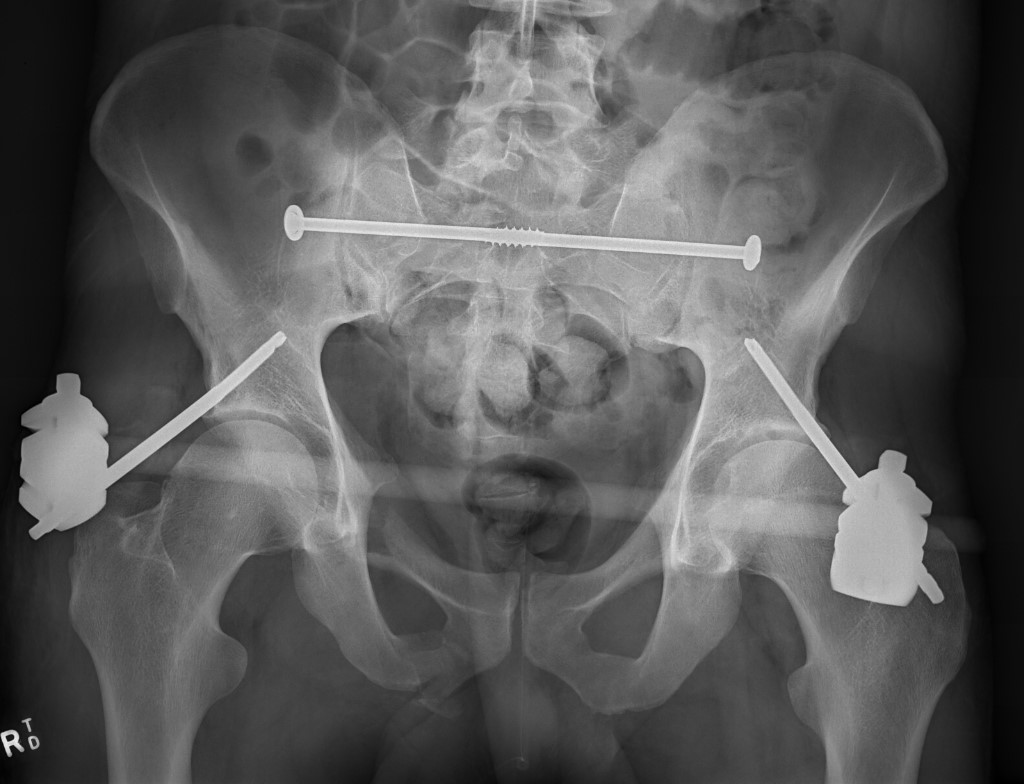

- external fixation

LC-1 with anterior external fixation Plating of bilateral pubic rami fractures